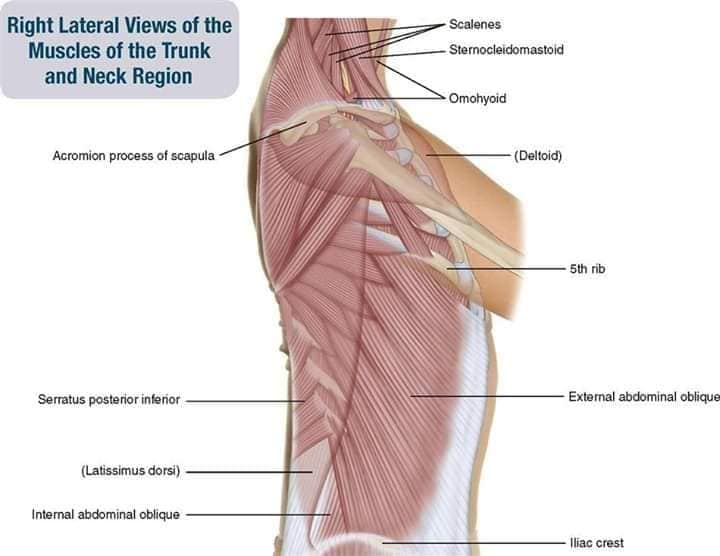

Шийні м'язи

Шийні м'язи мають важливе значення для підтримки голови і забезпечення її рухів.

М'язи бічної групи

М'язи, що повертають голову: Стерноклейдомастоїдний м'яз: один з найважливіших м'язів, який дозволяє здійснювати повороти і нахили голови. Він походить від грудини та ключиці і прикріплюється до соскоподібного відростка скроневої кістки.

Спинні м'язи

Спинні м'язи виконують функції підтримки хребта, а також дозволяють здійснювати рухи тулуба.

М'язи, що ведуть лопатку до хребта: Широкий м'яз спини: великий м'яз, що розташований в нижній частині спини. Він відповідає за рухи плечей і лопаток, а також за розширення верхньої частини тулуба.